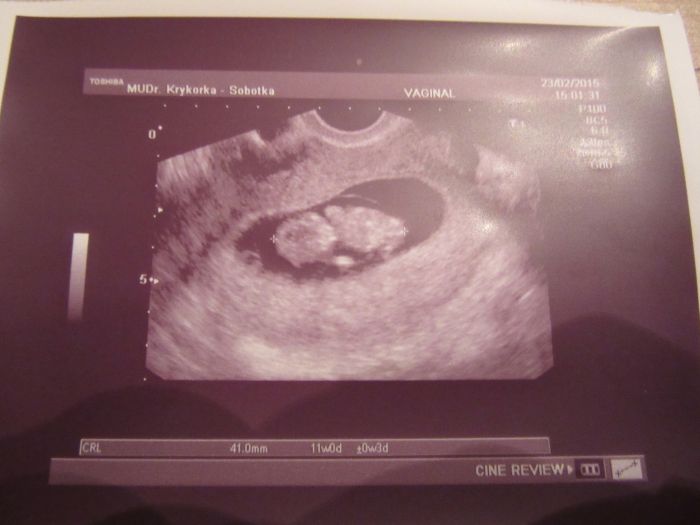

Holčiny zapomněla jsem na fotečku, tak přikládám toho našeho prďolínka.

To je krásná fotečka, o to víc se těším na svou kontrolu až našeho drobka taky uvidím

[707043]Kači, on nám ukazuje záda nebo se mi to zdá?

Hlavně, že je vše jak má být!